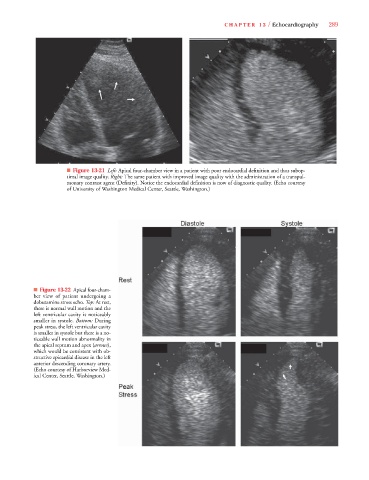

■ Figure 13-21 Left: Apical four-chamber view in a patient with poor endocardial definition and thus subop-

timal image quality. Right: The same patient with improved image quality with the administration of a transpul-

monary contrast agent (Definity). Notice the endocardial definition is now of diagnostic quality. (Echo courtesy

of University of Washington Medical Center, Seattle, Washington.)

■ Figure 13-22 Apical four-cham-

ber view of patient undergoing a

dobutamine stress echo. Top: At rest,

there is normal wall motion and the

left ventricular cavity is noticeably

smaller in systole. Bottom: During

peak stress, the left ventricular cavity

is smaller in systole but there is a no-

ticeable wall motion abnormality in

the apical septum and apex (arrows),

which would be consistent with ob-

structive epicardial disease in the left

anterior descending coronary artery.

(Echo courtesy of Harborview Med-

ical Center, Seattle, Washington.)